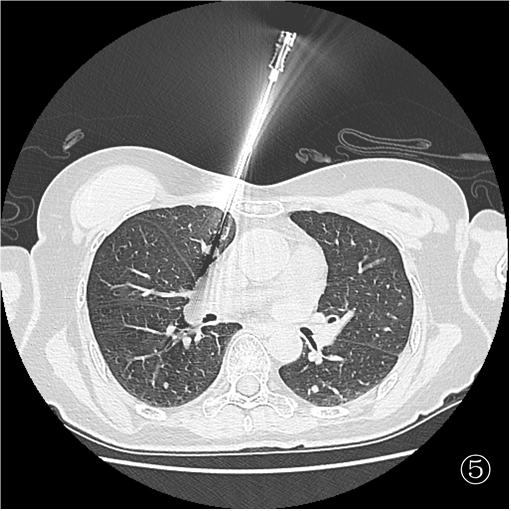

患者俯卧定位扫描(图③):由于胸腔及肺组织受压,左肺占位距离膈肌<1 cm,行穿刺活检必然损伤膈肌,可能造成严重并发症。于是决定经胸前穿刺右肺占位活检(图④),但由于病灶小于 1 cm 且邻近大血管,必须精准制导(图⑤)。穿刺后扫描局部少许出血,未见气胸(⑥)。

难点在于肺部占位较小(均<1 cm), 左肺占位穿刺相对安全,但由于俯卧位时病灶邻近膈肌,穿刺势必损伤膈肌。右肺占位穿刺风险较大(邻近重要大血管),故穿刺术前须精准定位,穿刺时须精准制导。另外,明确诊断后严格遵循循证医学证据科学治疗。